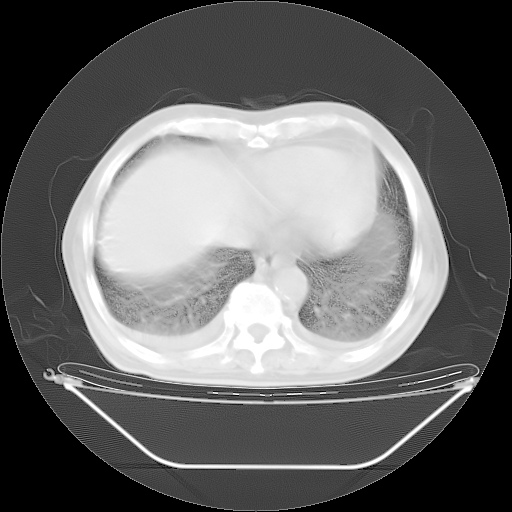

胸腹部CT,诊断意见:左上肺叶钙化灶、左侧胸膜局限性增厚并钙化、胆囊炎。描述部分肺组织呈磨玻璃样改变。